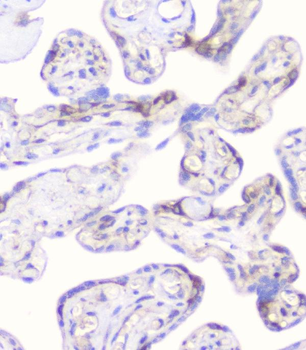

100 μg - FOXP3 antibody [orb34127]Featured

ELISA, ICC, IF, IHC-P, WB

Human, Mouse, Rat

Rabbit

Polyclonal

Unconjugated